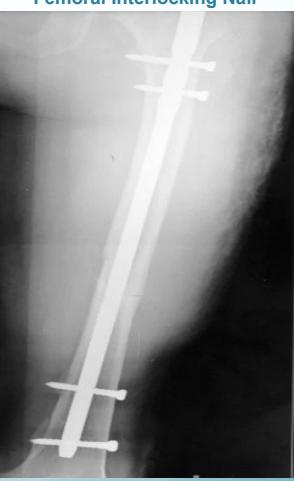

Inter-locking Nail

- Indications: Treatment of fractures of long bones

- Advantages:

- Minimally invasive

- Does not disturb fracture hematoma

- Allows early weight-bearing on lower limb